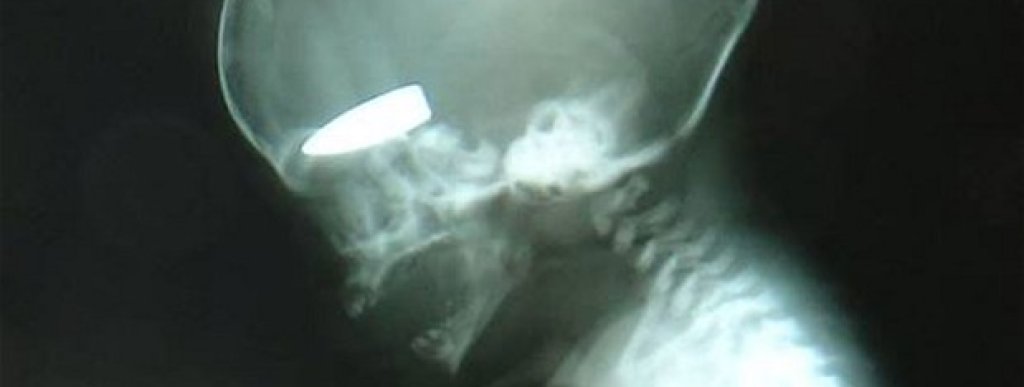

"Каквито рани имаха пациентите, които ни водеха сутрин, такива имаха и тези, които приемахме през деня. Това беше някаква игра", заяви хирургът. "Един ден идваха хора с рани в слабините, друг ден бяха ранени в лявата страна на гърдите, а на третия - простреляни във врата", разказва лекарят и допълва, че следващата рана е най-лошото, което е виждал в кариерата си. "Двадесет години лекувам хора във военни зони, но никога досега не съм виждал някой да убива бременни жени с цел. Пациентките бяха носени с огнестрелни рани в корема, не мога да ви опиша колко е ужасно това", разкрива хирургът, който пет седмици е спасявал хора в Сирия.